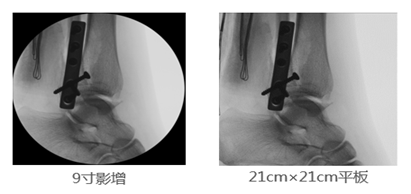

2、成像視野:在圖像尺寸方面, 9英寸平板與9英寸影增相比,平板探測(cè)器成像為“方形”,較同尺寸的影像增強(qiáng)器的“圓形”成像而言,有效視野面積擴(kuò)大了22%,使醫(yī)生的觀察視野更加開(kāi)闊,極大的提高了手術(shù)的效率,同時(shí)提高了各種手術(shù)的安全性。